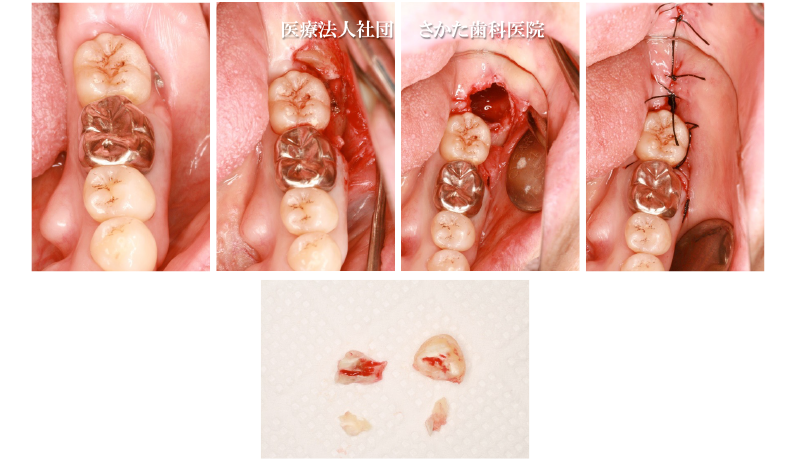

「親知らず」を神経から引き離す処置をしました。

神経損傷のリスクを回避するためです。

- 安全・安心な抜歯です

当院では下アゴの「親知らず」だけで年間約30本、開業以来約500本の抜歯を行ってきました。

抜歯による神経損傷などを含む重篤な偶発症は発生しておりません。- 抜歯やインプラントなど手術に対する恐怖心や不安感を少しでも和らげる手段として「笑気吸入鎮静法」を採用しております。